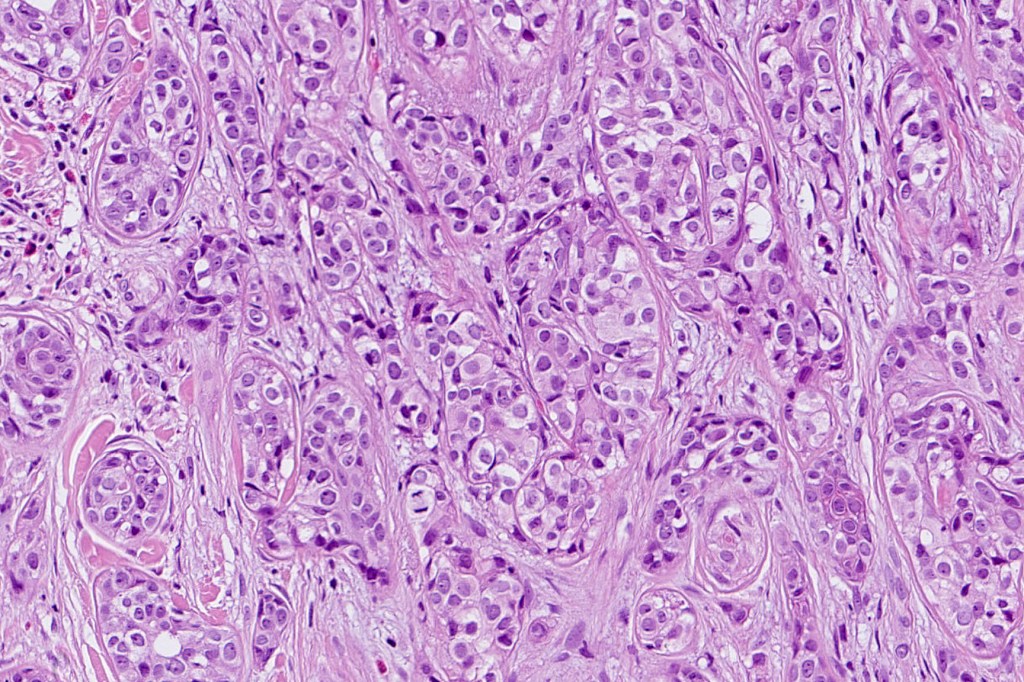

•Widely infiltrating biphasic tumor

•Superficial SCC

•Adenocarcinoma in deeper reaches

•Variable pleomorphism and mitotic activity

•Deep part may show both ducts and glands

•Often extends to the subcutaneous fat

•Perineural infiltration is commonly seen